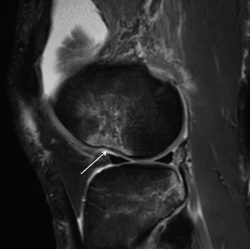

Figura 2. Radiografía anteroposterior de una rodilla derecha, donde puede apreciarse una fractura de Segond (flecha blanca).

- Radiografía (Rx): la imagen radiológica más característica que se relaciona con la lesión del LAL es la fractura de Segond, aunque esta solo está presente en un 1,25% de los pacientes con lesión de LCA(34)(Figura 2).

Se ha demostrado la correlación entre los hallazgos en ecografía y RM con alto grado de pivot shift en lesiones de LAL(36,40). Mediante esta exploración pueden detectarse tanto la lesión propiamente dicha del LAL, como la fractura de Segond y otros signos indirectos como la impactación del cóndilo femoral lateral (Figura 3).

Figura 3. Imagen sagital de resonancia magnética del cóndilo femoral externo en la que puede apreciarse el signo de impactación (nocht sign, flecha blanca). Puede interpretarse como signo indirecto de afectación del ligamento anterolateral .